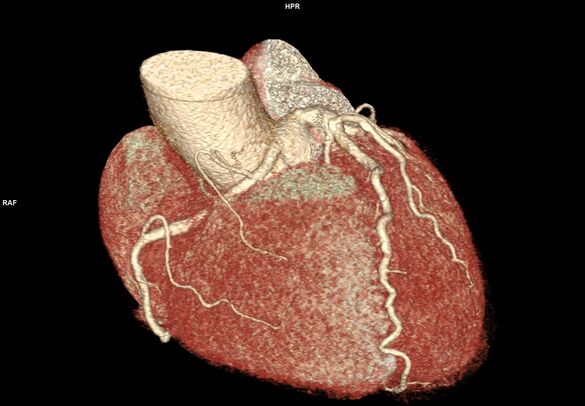

„Mit dem neuen Computertomographen steht uns nun auch die Möglichkeit zur Verfügung, Patienten nicht-invasiv am Herzen zu untersuchen. Herzkranzgefäße können durch das Herz-CT auf Engstellen und Herzkranzgefäßverkalkungen untersucht werden. So kann in ausgewählten Fällen eine Herzkatheteruntersuchung über die Leiste oder dem Arm durch ein Herz-CT vermieden werden. Die Behandlung wird für unsere Patienten so angenehm und auch risikoarm.“

„Neben den konventionellen 2D-Daten wird auch ein 3D-Modell des Herzens zur besseren Veranschaulichung erstellt,“ sagt Baumann. Der abschließende Befund würde in der Regel noch am selben Tag erstellt und dem behandelnden Arzt zugeschickt.

3D-Darstellung des Herzens